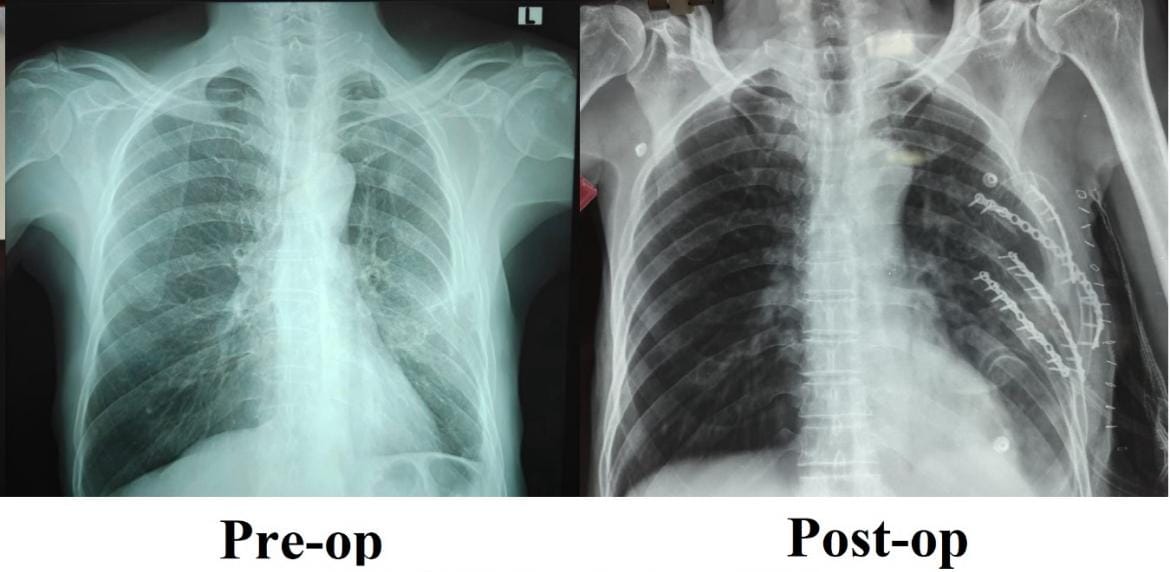

Recognising the need for surgical intervention, the trauma team led by Dr. Vijayan P, Associate Professor, Department of General Surgery, undertook a specialised rib fixation procedure to realign and stabilise the fractured ribs, enabling proper anatomical healing.

Following surgery, the patient showed rapid and marked improvement. Breathing became comfortable, mobility improved significantly with minimal pain, and the patient was able to resume routine activities with renewed confidence.